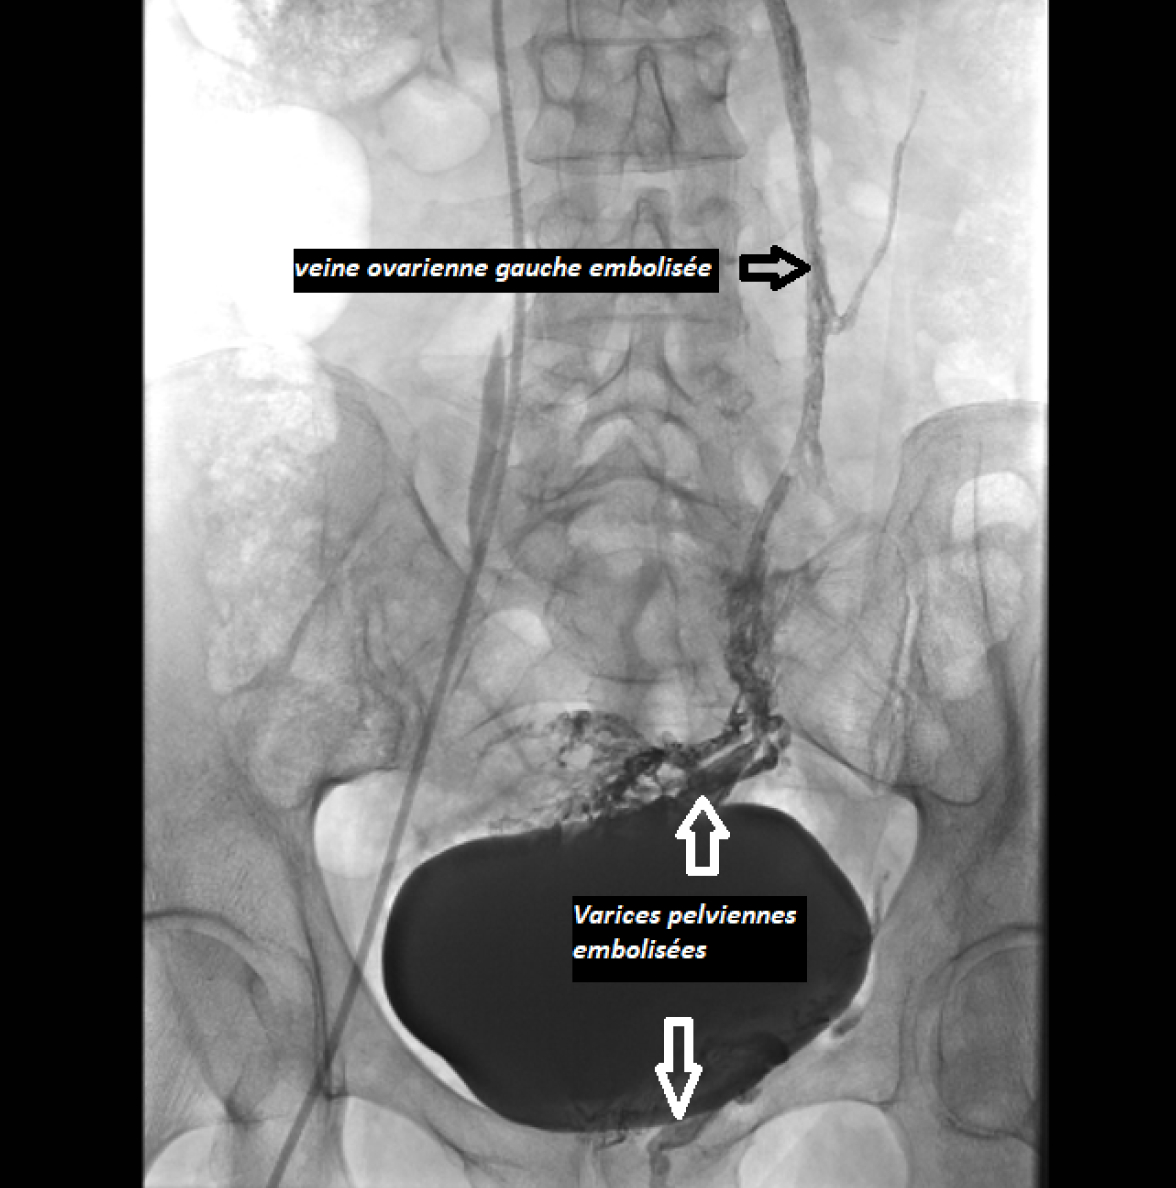

L’embolisation des varices pelviennes est un geste de radiologie interventionnelle qui vise à boucher les veines incontinentes (veines pelviennes, veines ovariennes) alimentant les varices via l’injection d’agents d’embolisation.

La phlébographie permet par ailleurs d’avoir des renseignements sur l’existence d’un syndrome de May Thurner ou de Nut-Cracker. Une fois la cause de l’incontinence et les varices individualisées, le radiologue interventionnel procède à l’embolisation par un agent liquide (colle biocompatible avec éventuellement un agent sclérosant en complément).

Un contrôle radiologique en temps réel est effectué du début à la fin de l’intervention. L’examen dure environ 1h, éventuellement plus longtemps si les varices sont dures à trouver ou si un stent doit être posé. Après l’embolisation, une autre série d’images est prise pour s’assurer que les veines nourricières ont été correctement obstruées. A la fin de l’intervention, vous êtes surveillées en salle de réveil puis en unité ambulatoire avant votre retour à domicile.